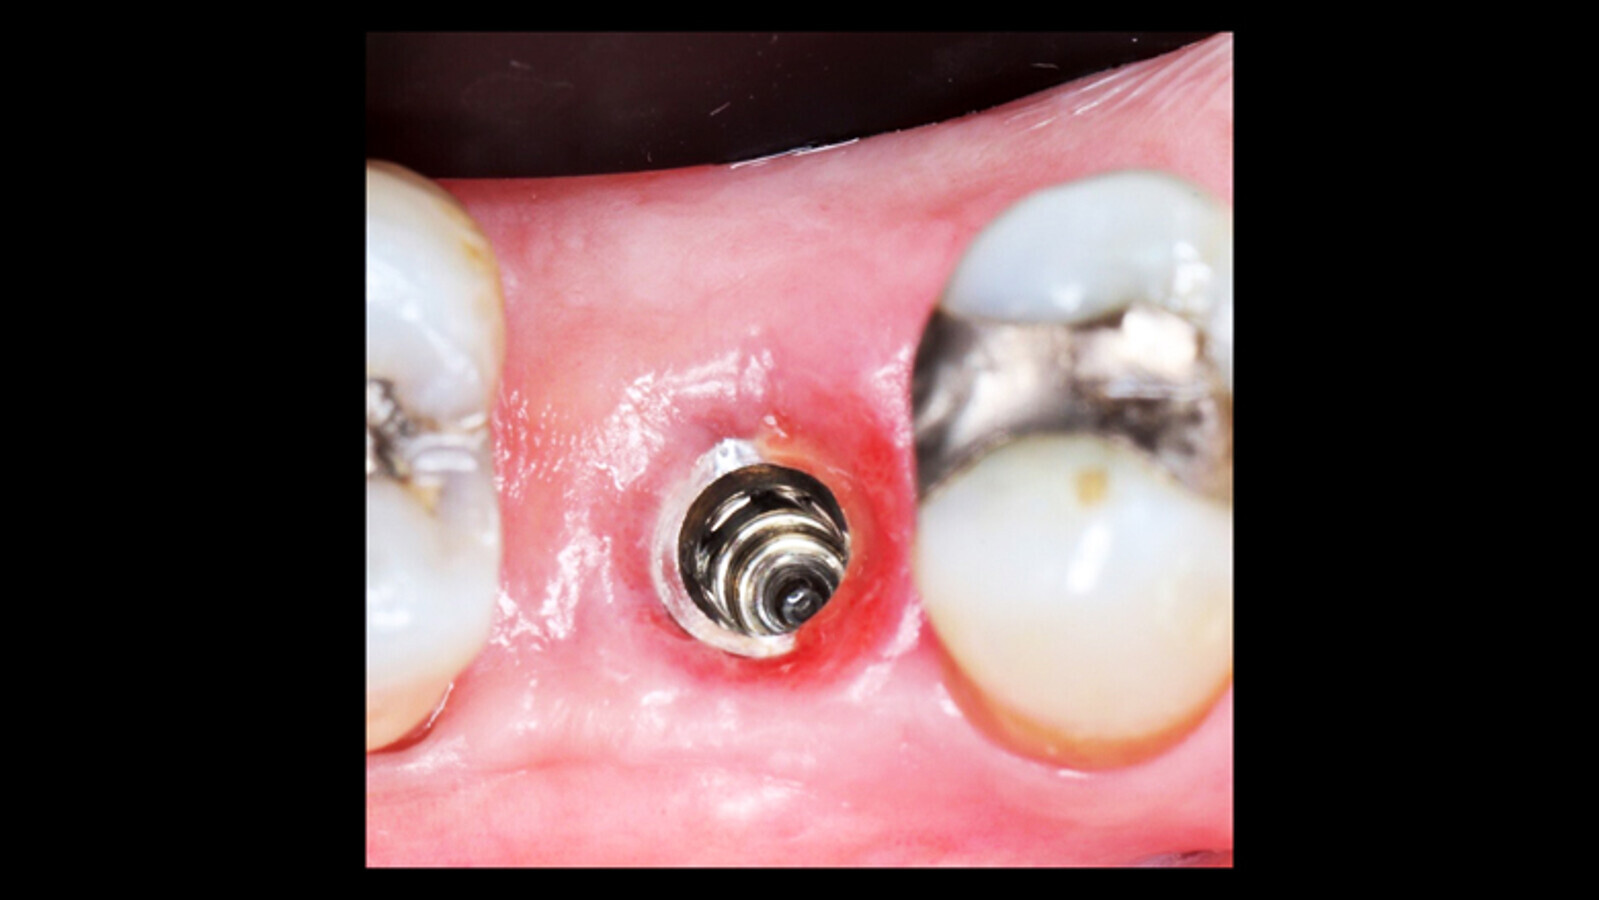

La biopsia reporta que el tejido epitelial se ve interrumpido en la longitud de sus capas y en el tejido conectivo subepitelial, presencia de infiltrado inflamatorio (abundan los linfocitos, macrófagos), focos hemorrágicos, edema intersticial, acúmulos hemorrágicos de necrosis tisular y colonias de candida. El estudio de cultivo arroja crecimiento de C. albicans (Figura 2).

Figura 2. El estudio de cultivo arroja crecimiento de C. albicans.

Posterior a los resultados se formula fluconazol MK tabletas 200 mg (Tecnoquímicas, Colombia) cada 7 días por 6 semanas.